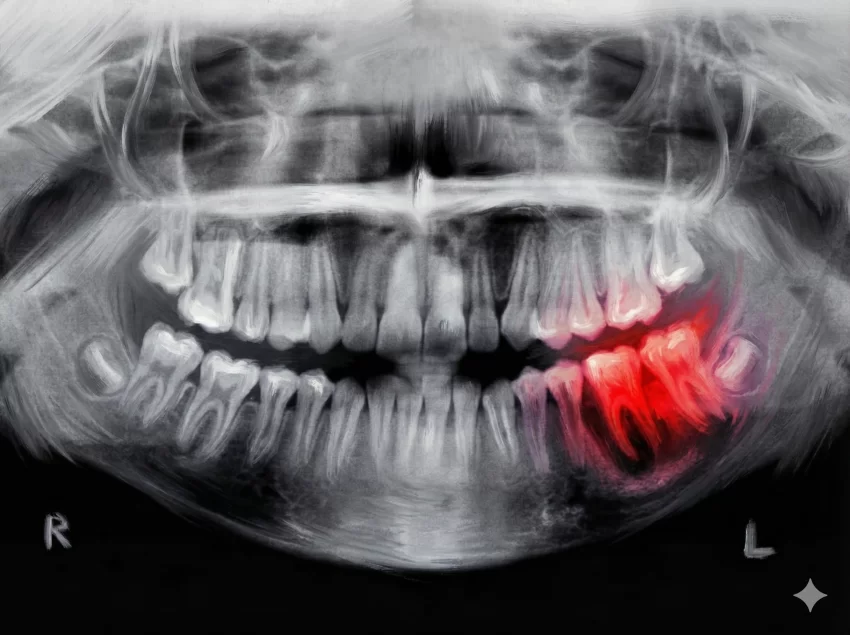

Bu devrim niteliğindeki gelişmenin temelinde, yıllardır süren titiz genetik araştırmalar yatıyor. Bilim insanları, dişlerin büyümesini engelleyen belirli bir antikoru keşfettiler: Uterine sensitization-associated gene-1 (USAG-1). Bu antikorun temel görevi, vücudun diş çıkarma potansiyelini kısıtlamaktır. 2021 yılında Kyoto Üniversitesi‘nden araştırmacılar, genellikle kanser tedavisinde kullanılan bir teknik olan “monoklonal antikor” yöntemini kullanarak USAG-1 antikorunun etkisini kırmayı başardılar.

Yapılan çalışmalar, bu antikorun baskılanmasının BMP (Kemik Morfogenetik Proteini) olarak bilinen moleküllerle etkileşime girerek diş büyümesini tetiklediğini gösterdi. Katsu Takahashi, USAG-1‘i baskılamanın diş büyümesine fayda sağladığını bildiklerini ancak bunun yeterli olup olmayacağını ancak deneylerle görebileceklerini belirtmişti. İlk olarak fareler ve gelincikler üzerinde yapılan testler, ilacın şaşırtıcı bir şekilde yeni dişlerin oluşumunu sağladığını kanıtladı. Gelinciklerin seçilme nedeni, diş yapılarının insanlarla benzerlik göstermesiydi.